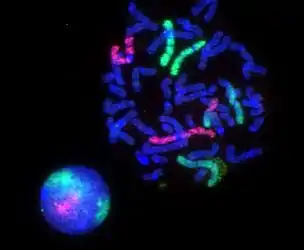

3D dual-color super-resolution microscopy with Her2 and Her3 in breast cells, standard dyes: Alexa 488, Alexa 568. LIMON microscopy Human lymphocyte nucleus stained with DAPI with chromosome 13 (green) and 21 (red) centromere probes hybridized (Fluorescent in situ hybridization (FISH))

Human lymphocyte nucleus stained with DAPI with chromosome 13 (green) and 21 (red) centromere probes hybridized (Fluorescent in situ hybridization (FISH)) Yeast cell membrane visualized by some membrane proteins fused with RFP and GFP fluorescent markers. Imposition of light from both of markers results in yellow color.